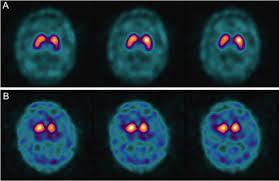

Normal And Abnormal Datscan Spect Images A Normal Datscan Spect Image Download Scientific Diagram